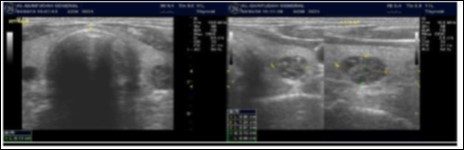

The reported prevalence of nodular thyroid disease depends on the population studied and the methods used to detect nodules 16. Our study population is unique as it is composed entirely of ESKD patients. We also used ultrasound as a method of detecting thyroid abnormalities. In our study the prevalence of thyroid nodular pathology as detected by ultrasound was found to be 57.6% mirror image what reported in the literature as it has been reported that nodules found on ultrasonography suggest a prevalence of 19 to 67%17, 18; and in other publications it has been reported to range from 50% to 70% 7, 8. Figure 3A below shows an Ultrasound detected thyroid nodule.

Figure 3A.Thyroid nodule

Thyroid nodule

The prevalence of thyroid nodule is also influenced by age. In one study, 30 % of subjects 19 to 50 years of age had an incidental nodule on ultrasonography19. However, from our work we found that the presence of nodules increases with age. This may explain the reported low incidence of thyroid nodule in the age group 19-50 years. Also, with the widespread use of sensitive imaging in clinical practice, incidental thyroid nodules are being discovered with increasing frequency.

High-resolution ultrasonography (USG) is the most accurate and cost-effective method for evaluating and observing thyroid nodules 3. Although there is some overlap between ultrasound appearance of benign and malignant nodules, certain USG features are helpful in differentiating the two. Iso-or hyper-echogenicity of the thyroid nodule in conjunction with a spongiform appearance is the most reliable criterion for benignity of the nodule on gray-scale ultrasound, Figure 4A. Other features like nodule size <1 cm, width > length, presence of hypoechoic or hyperoechoic halo around the nodule, Figure 4A and Figure 4B, caused by fibrous capsule compressing thyroid tissue, and coarse/curvilinear calcification are less specific but may be useful ancillary signs4 ,6.  "Ring down" or "comet-tail" artifact or sign is typical of benign cystic colloid nodule, Figure 520.  Perinodular flow or spoke-and-wheel-like appearance of vessels on color Doppler examination is characteristic of a benign thyroid nodule. However, this flow pattern may also be seen in thyroid malignancy. A complete avascular nodule is very unlikely to be malignant 4.